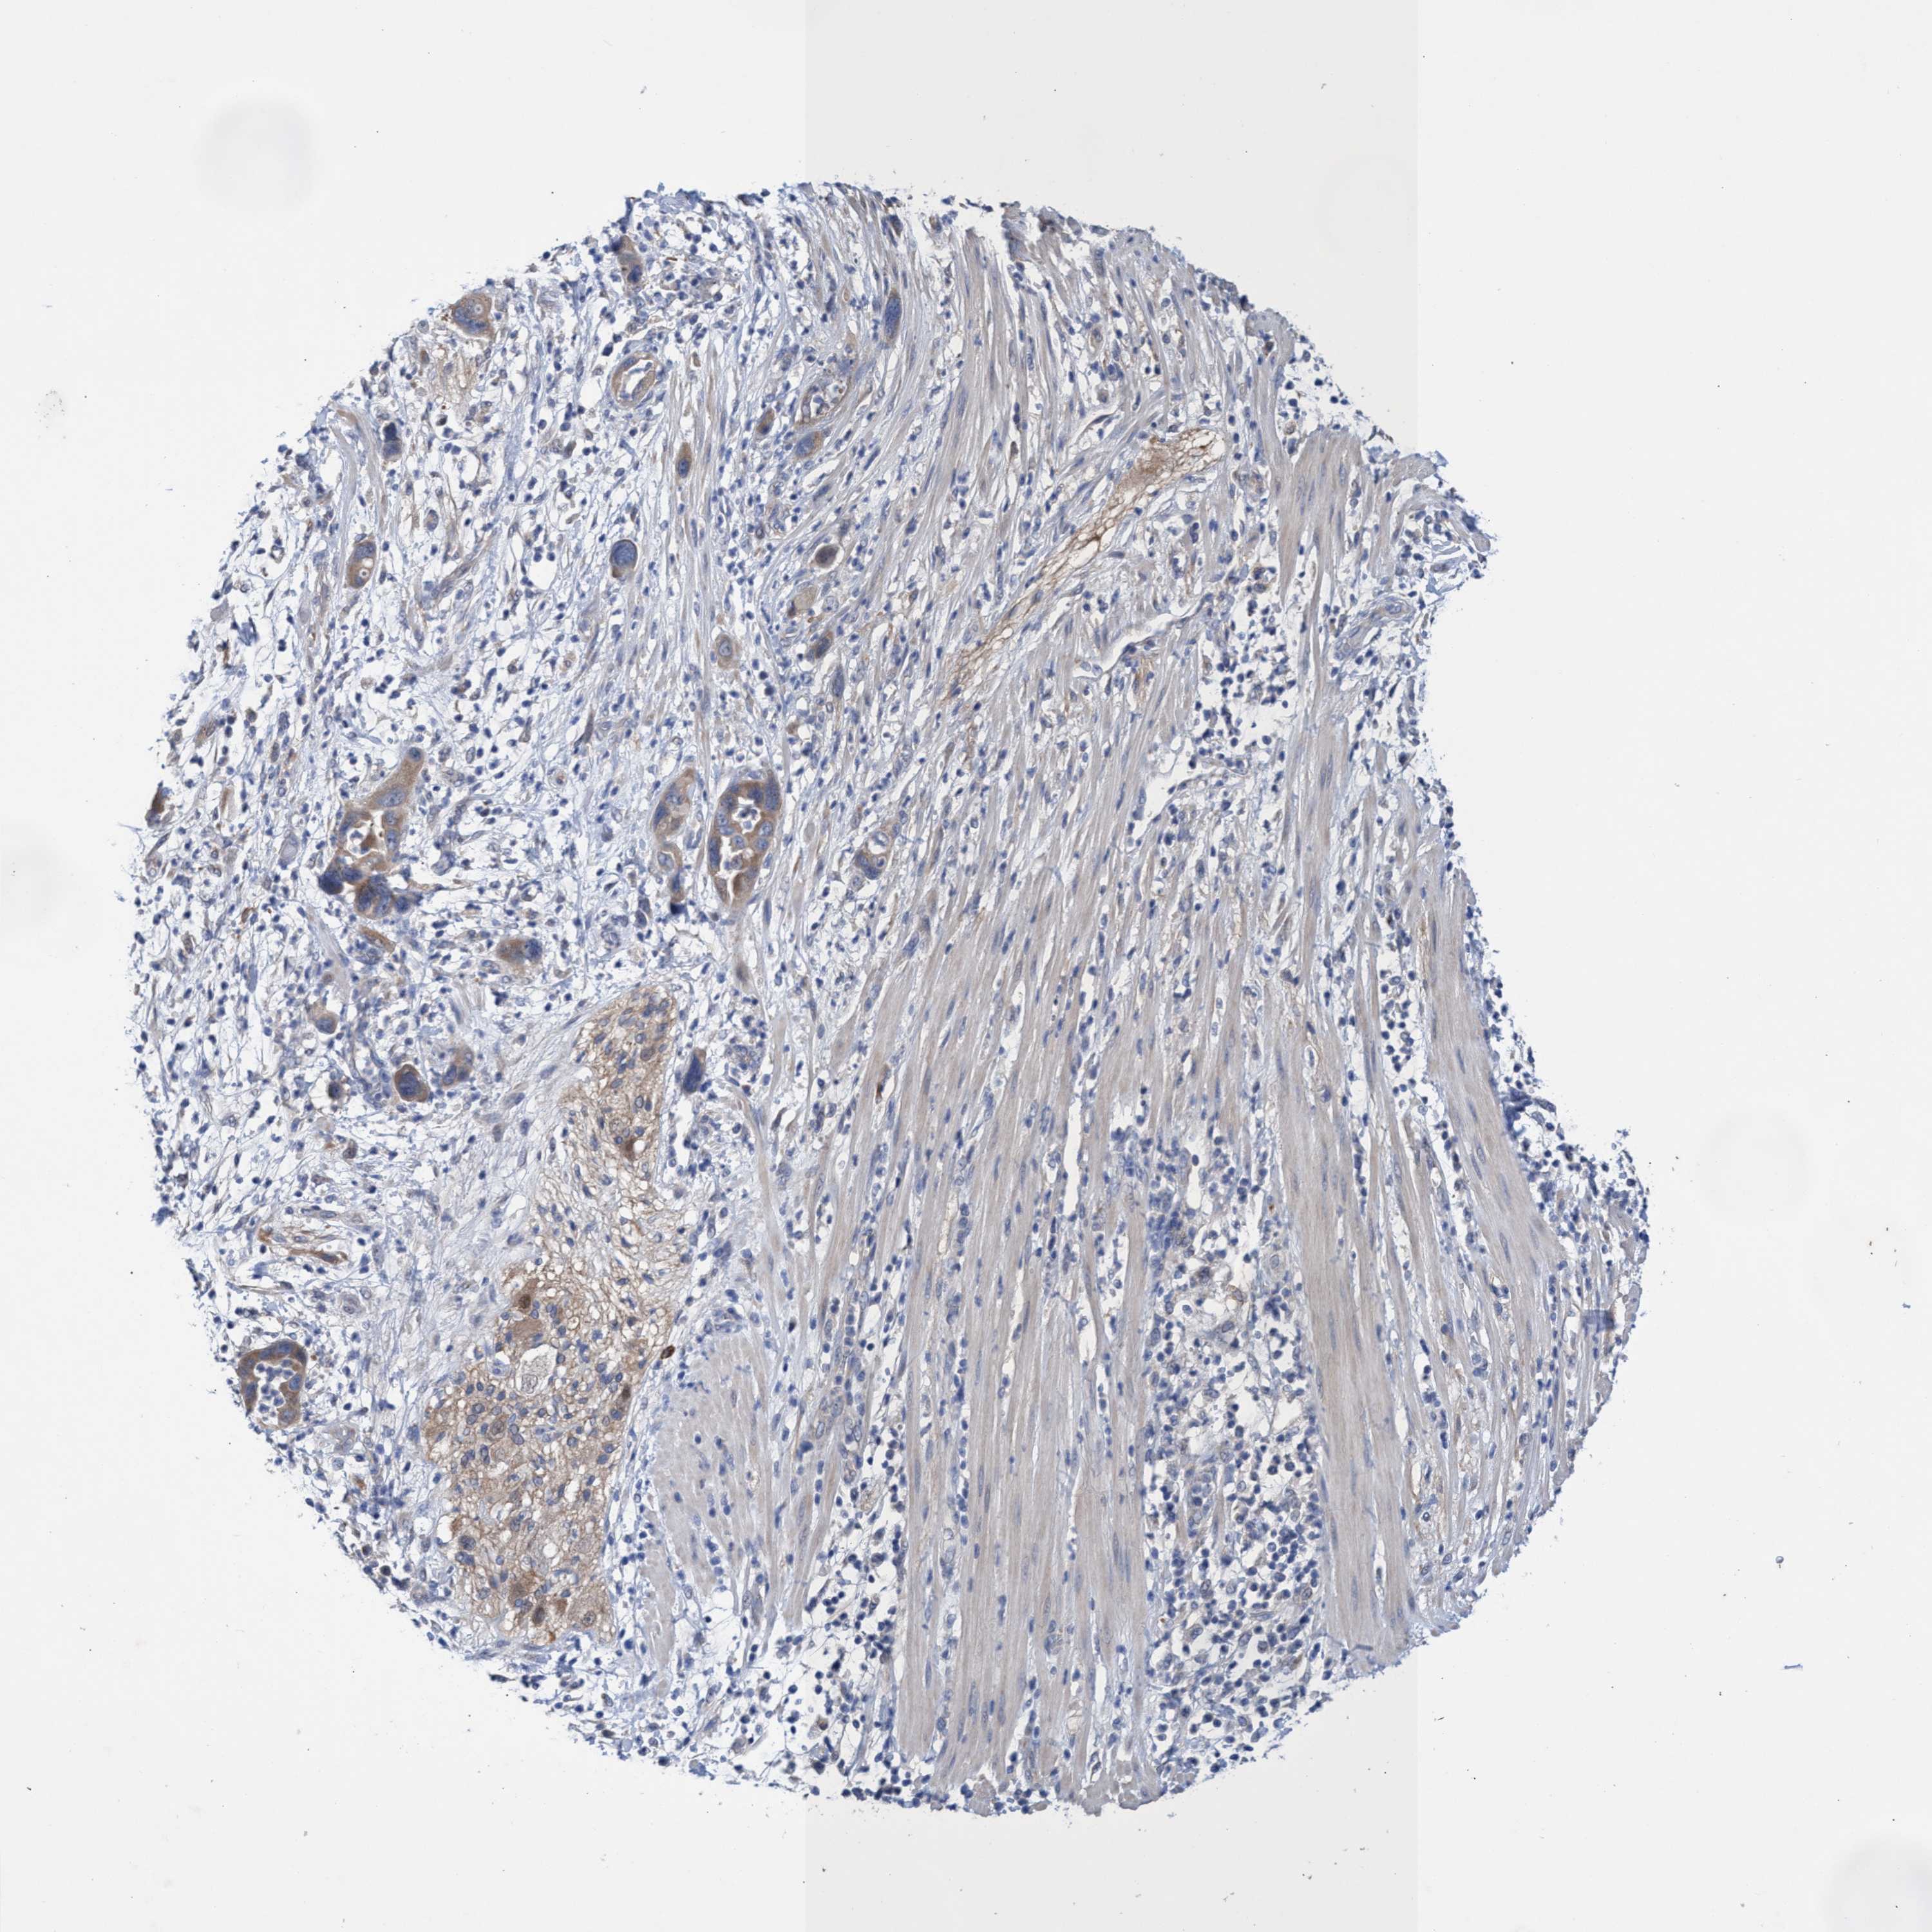

PANCREATIC CANCER - Protein expressioni

A mouse-over function shows sample information and annotation data. Click on an image to view it in a full screen mode. Samples can be filtered based on level of antibody staining by selecting one or several of the following categories: high, medium, low and not detected. The assay and annotation is described here.

Note that samples used for immunohistochemistry by the Human Protein Atlas do not correspond to samples in the TCGA dataset.

Antibody stainingi

Antibody staining in the annotated cell types in the current human tissue is reported as not detected, low, medium, or high, based on conventional immunohistochemistry profiling in selected tissues. This score is based on the combination of the staining intensity and fraction of stained cells.

Each image is clickable and will lead to virtual microscopy that enables deeper exploration of all samples and also displays staining intensity scores, fraction scores and subcellular localization as well as patient and tissue information for each sample.

Antibody HPA020610

Antibody HPA021520

Adenocarcinoma, NOS